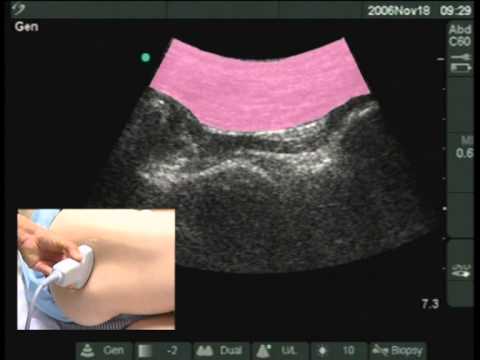

В этом видео я рассказываю про синдром грушевидной мышцы, защемление седалищного нерва и лечебно-диагностическую блокаду при этих состояниях. Обсуждаем показания, противопоказания, побочные эффекты и на сколько помогает данное лечение. В этом видео я не демонстрирую технику самой блокады грушевидной мышцы, но показываю как выглядит блокада под УЗИ навигацией. Блокаду выполняли с дипроспаном и лидокаином. Также есть отзыв пациентки о блокаде грушевидной мышцы. Остались вопросы? У нас есть специальный Telegram-канал, где вы можете задать вопросы нашим специалистам Smart Clinic. Получите персонализированные советы и поддержку онлайн от профессионалов! Ссылка на канал: Мы проводим оценку ваших МРТ позвоночника с целью оценки вероятности резорбции. Чтобы получить профессиональную консультацию и оценить потенциальную эффективность лечения, заполните форму и отправьте нам МРТ-исследование - Мы НЕ назначаем лечение онлайн. Меня зовут Ковзелев Павел Дмитриевич, я врач невролог из Санкт-Петербурга и медицинский руководитель Смарт Клиник. Связаться со мной: / nevrolog_kovzelev . ЗАПИСАТЬСЯ НА ПРИЕМ: 🌐 ☎️ +7-812-332-09-42 🗺️ г. Санкт-Петербург, ул. Набережная Обводного канала, 108А. 📁СКАЧАТЬ БЕСПЛАТНОЕ РУКОВОДСТВО ОТ НАШИХ ВРАЧЕЙ: • БОЛИ В СУСТАВАХ - • РЕЗОРБЦИЯ ГРЫЖИ ДИСКА - • ГОЛОВНЫЕ БОЛИ -